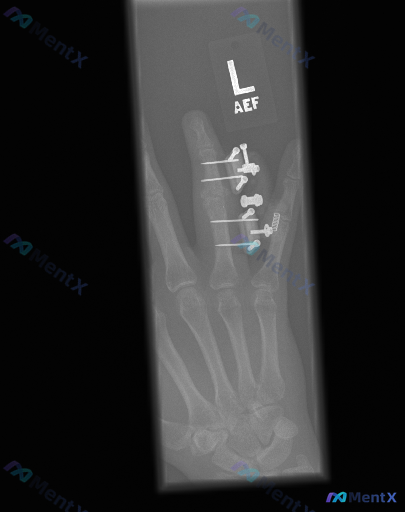

左手无名指内固定术后X光:只看得到手术痕迹,还是藏着其他异常?

整理到一张左手正位X光的读片资料,先看核心信息:

- 图像范围:仅显示手掌中、环、小指及部分腕骨

- 明确背景:无名指(环指)近节、中节指骨区可见克氏针、钢板/连接装置及螺旋状金属固定,跨越近侧指间关节(PIP)

- 客观发现:

- 金属钉道处骨皮质中断(医源性)

- 无名指局部软组织影明显增厚

- 其余可见掌指骨皮质连续,非术区骨小梁尚可

- 未受固定影响的关节间隙对位好

这份资料里特别提到“存在异常”,而不是单纯报告“术后改变”。